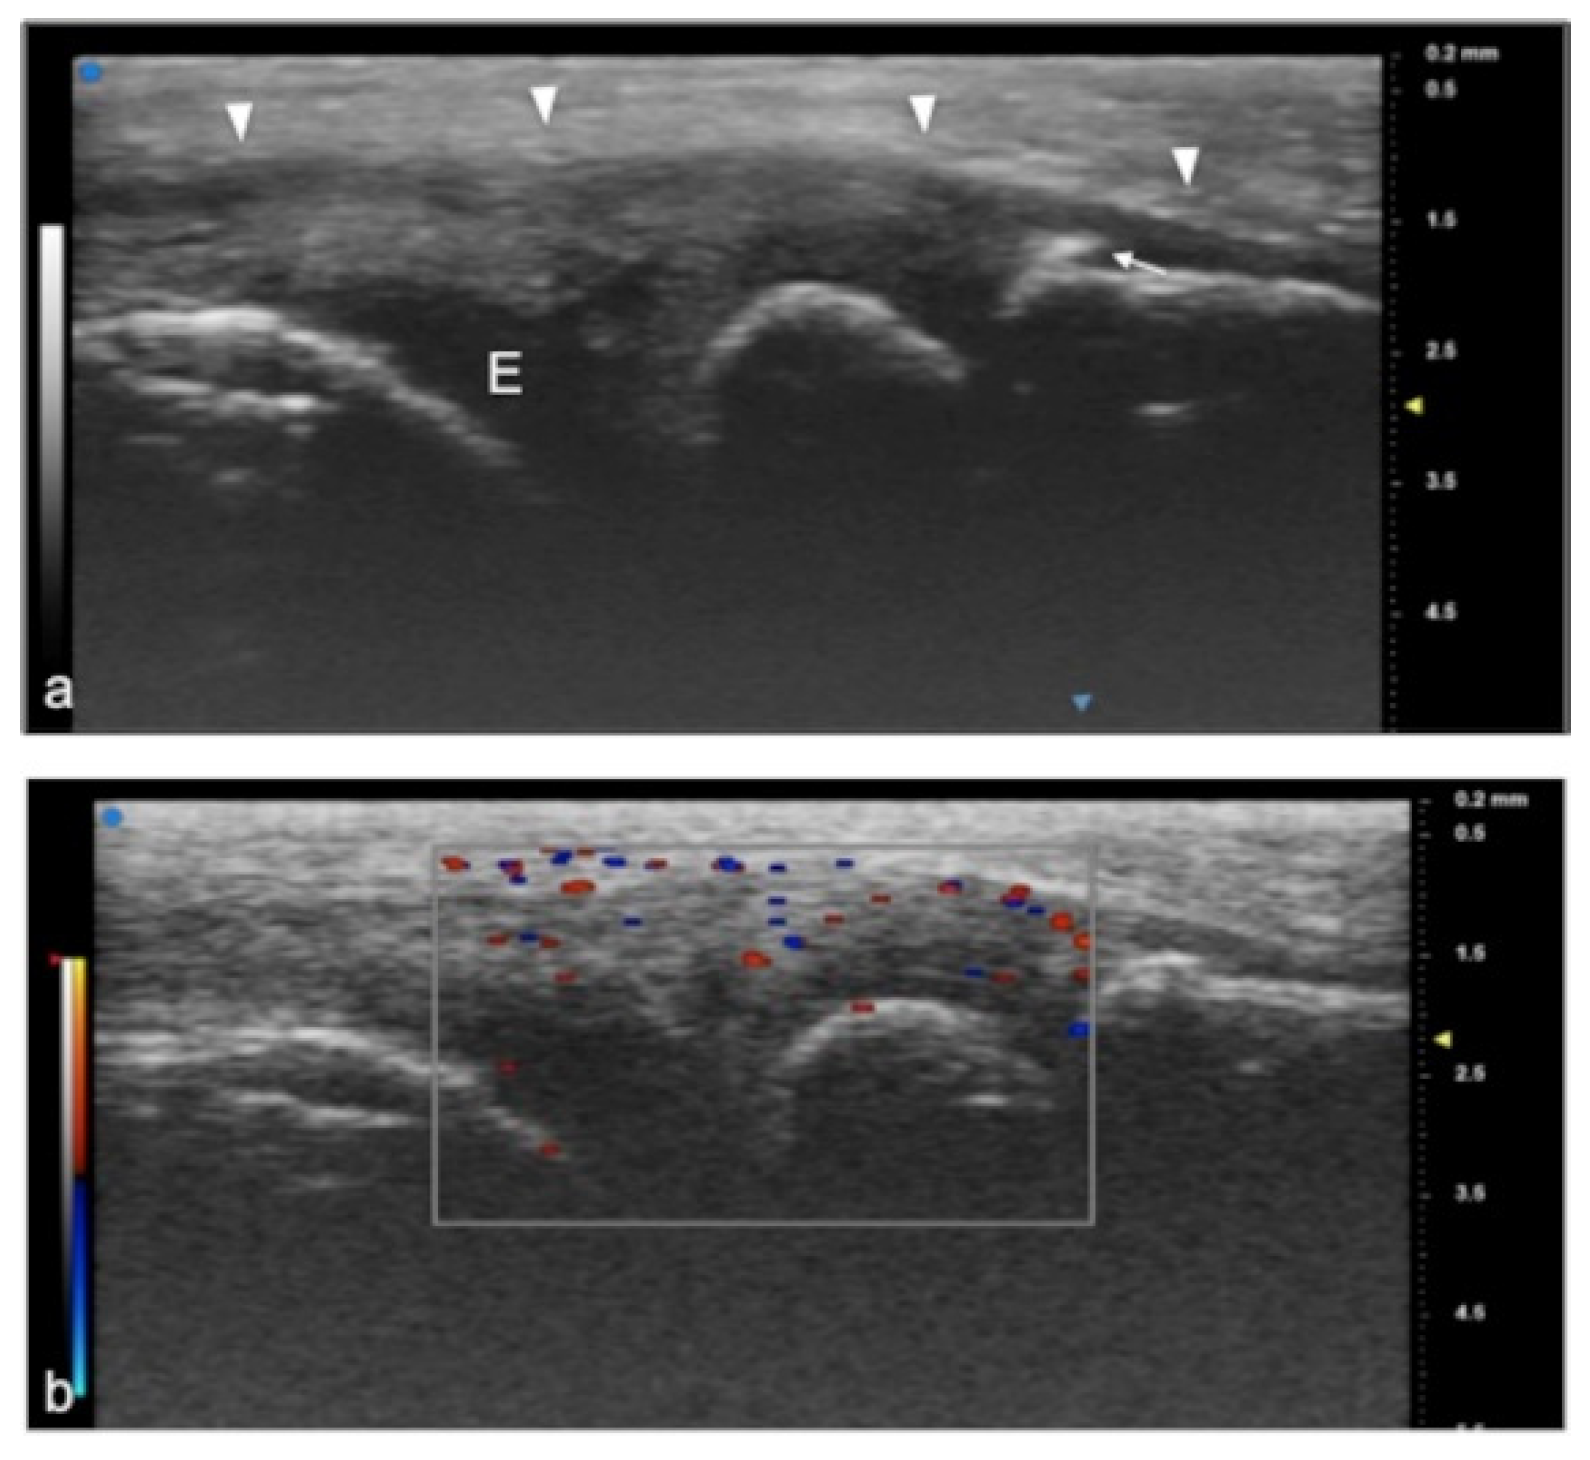

Figure 4.

Juvenile idiopathic arthritis (JIA). UHFUS gives clear details of pathological findings in pediatric patients with JIA. In (a), articular effusion (E) at the level of the metacarpal–phalangeal joint (MET-PP). In (b), osseous erosions at the level of the metacarpal head (white arrows).

Figure 5.

Juvenile idiopathic arthritis. UHFUS gives clear details of pathological findings in pediatric patients with JIA. In (a), articular effusion (E) at the level of wrist and enthesophyte (white arrow). Thickened capsule (arrowheads) in (a) presenting with an increased Doppler signal (white square) in (b).